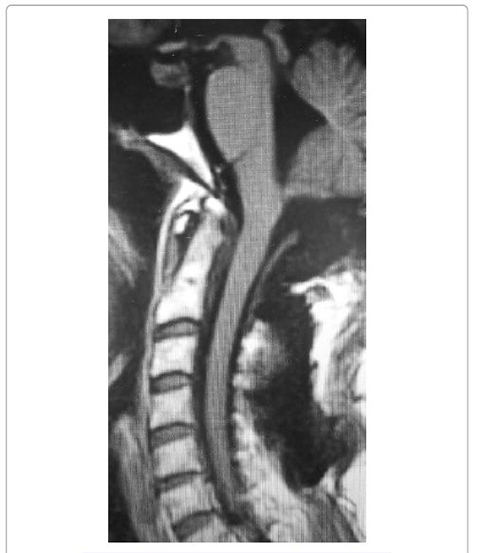

患者取俯卧位,行枕下颅骨切除术和C1椎板切除术。通过后外侧入路,在没有任何术中事件的情况下,实现了肿瘤的完全切除(图3和图4)。术后恢复正常,除了持续几天的打嗝。手术标本病理报告为“I级脑膜瘤”。

图3 :术后矢状位对比增强T2WI MRI扫描

图4 :术后矢状位T1WI MRI扫描